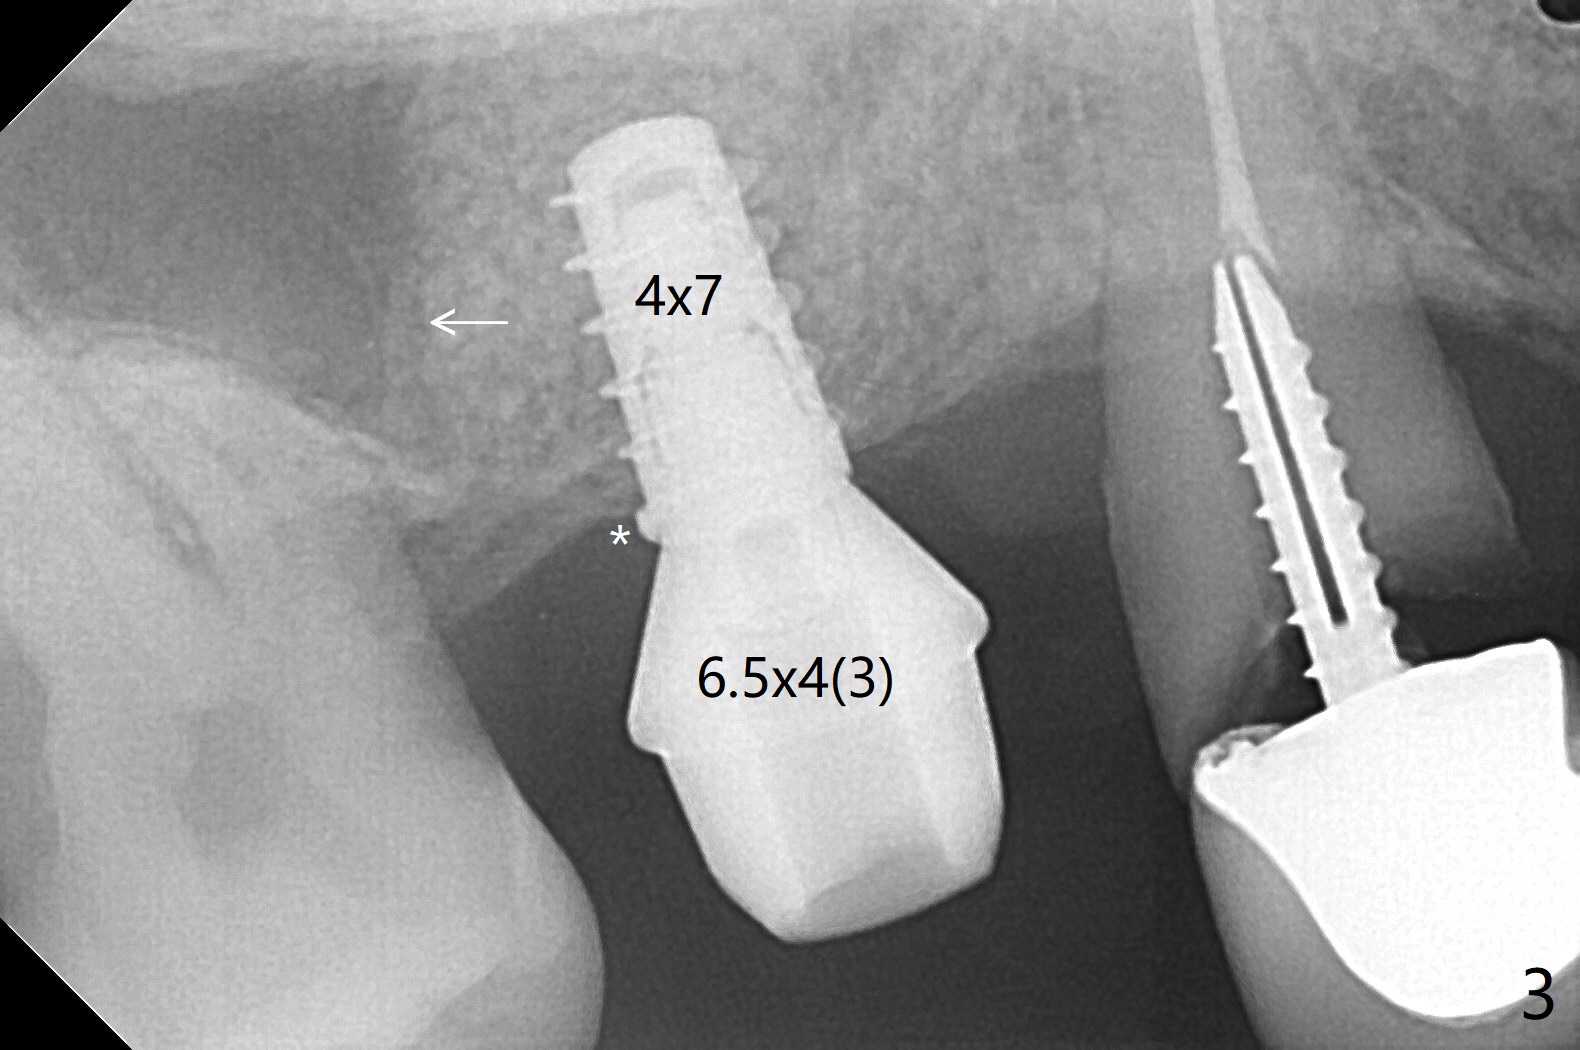

49岁女(个子小)牙齿问题多,同意先做右上5,6种植,6骨质高度1-2毫米,一个月前因动脉出血外提升失败。今天她回来做内提升,同意如果条件合适,同期徒手植牙(将来做一个磨牙牙冠),事先服用阿奇霉素。使用粘性骨粉和报废植体做内提(图一:*),最后植入4x7毫米植体(35Ncm),近中颊侧平牙槽嵴(图二:*),其余骨上 (图三: *),不敢植入太深,怕掉入上颌窦。第二个预防掉入上颌窦措施是利用大号基台(图三),然后在基台周围放置骨粉(图四:*,五),缝合,牙周敷料。伤口愈合后,准备制作树脂敷料,防止植体和基台往口腔脱落。术后五天复诊,无上颌窦炎症,牙周敷料稳定。她再回来时已经术后4.5个月,植体稳定,更换基台没有疼痛(图六,七),口腔卫生极佳,使用水牙线,不敢患侧刷牙。